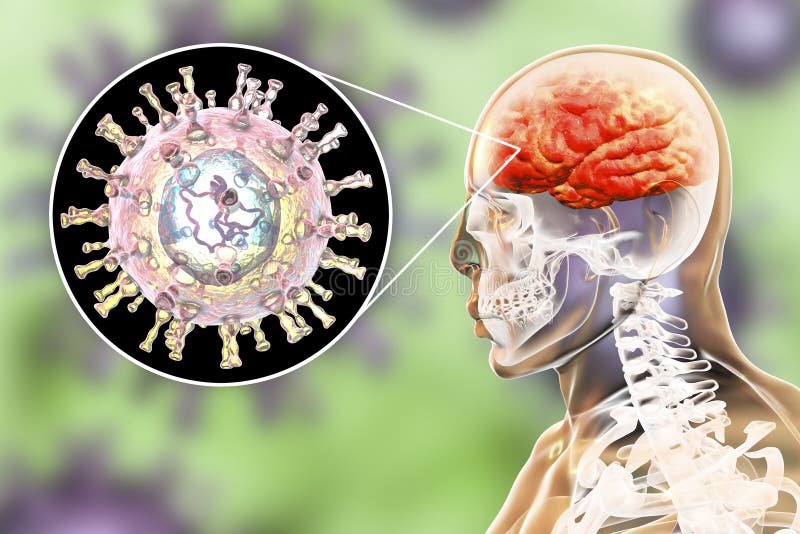

Медицинские снимки и изображения опоясывающего герпес вируса

Раздел: Фотодневник открытий